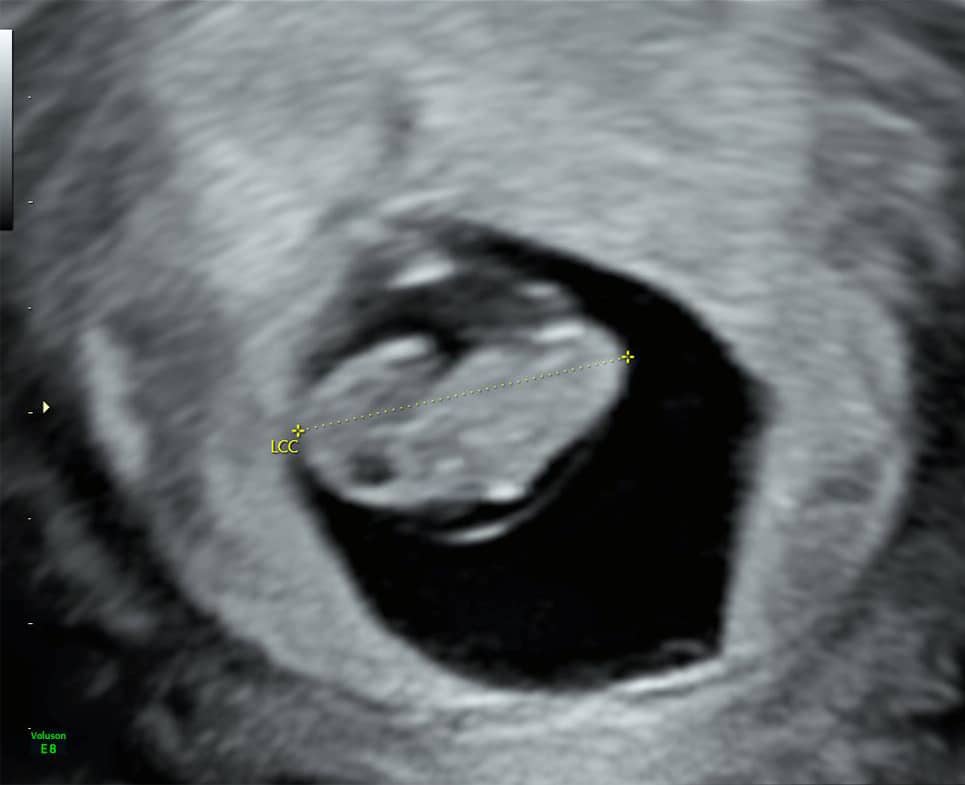

1. L’échographie de datation (7 à 9 SA , soit environ 1 mois 1/2 de grossesse)

C’est souvent la première rencontre avec votre bébé.

Réalisée par voie abdominale ou parfois par voie endovaginale , elle permet :

• De confirmer la grossesse et sa localisation (intra-utérine)

• De vérifier le nombre d’embryons (grossesse simple ou gémellaire)

• De mesurer la longueur de l’embryon pour dater précisément la grossesse

• D’observer l’activité cardiaque

C’est une échographie brève, mais très importante pour poser les bases du suivi de grossesse.